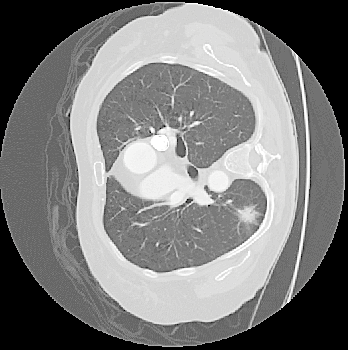

- Abstract: An exploration of whether conventional detection methods of lung cancers in low dose spiral CT scan could be improved using curvature features. In general, a large source of inaccuracy in detection rates can be attributed to irrelevant anatomical structures such as blood vessels. Often these irrelevant anatomical structures have different shape characteristics from lung nodules. For example lung nodules tend to appear bloblike as oppose to blood vessels, which appear cylindrical, or organ walls, which appear planelike. These curvature features were determined using eigenanalysis of the local second order image Hessian of each voxel, where the principal values are indicative of the local shape and provide more information than analysis performed on first derivatives alone.

- Method Overview: In each CT scan, the internal 3D lung volume was isolated using standard thresholding of pressurevalues ranges associated with lung parenchyma. The remaining voxels were conjoined using a connected components method, implemented through a union-find method, with small and isolated components removed. The remaining gaps were filled in using a standard 3D image closure method. First and second order partial derivatives were computed using Deriche filters, chosen for their stability and suitability in medical image scans. Then, for each of the voxels in the internal volume of the lung the local second order Image Hessian was generated and analyzed for preferred directions using eigenanalysis. This information was then used to weight the contribution of each voxel to standard lung nodule detection methods, to determine if giving stronger weight to voxels with local blob-like shape improved detections results.

Top row: An image slice demonstrating the lung Isolation process, enacted on a low dose spiral CT scan taken from the LIDC-IDRI database.